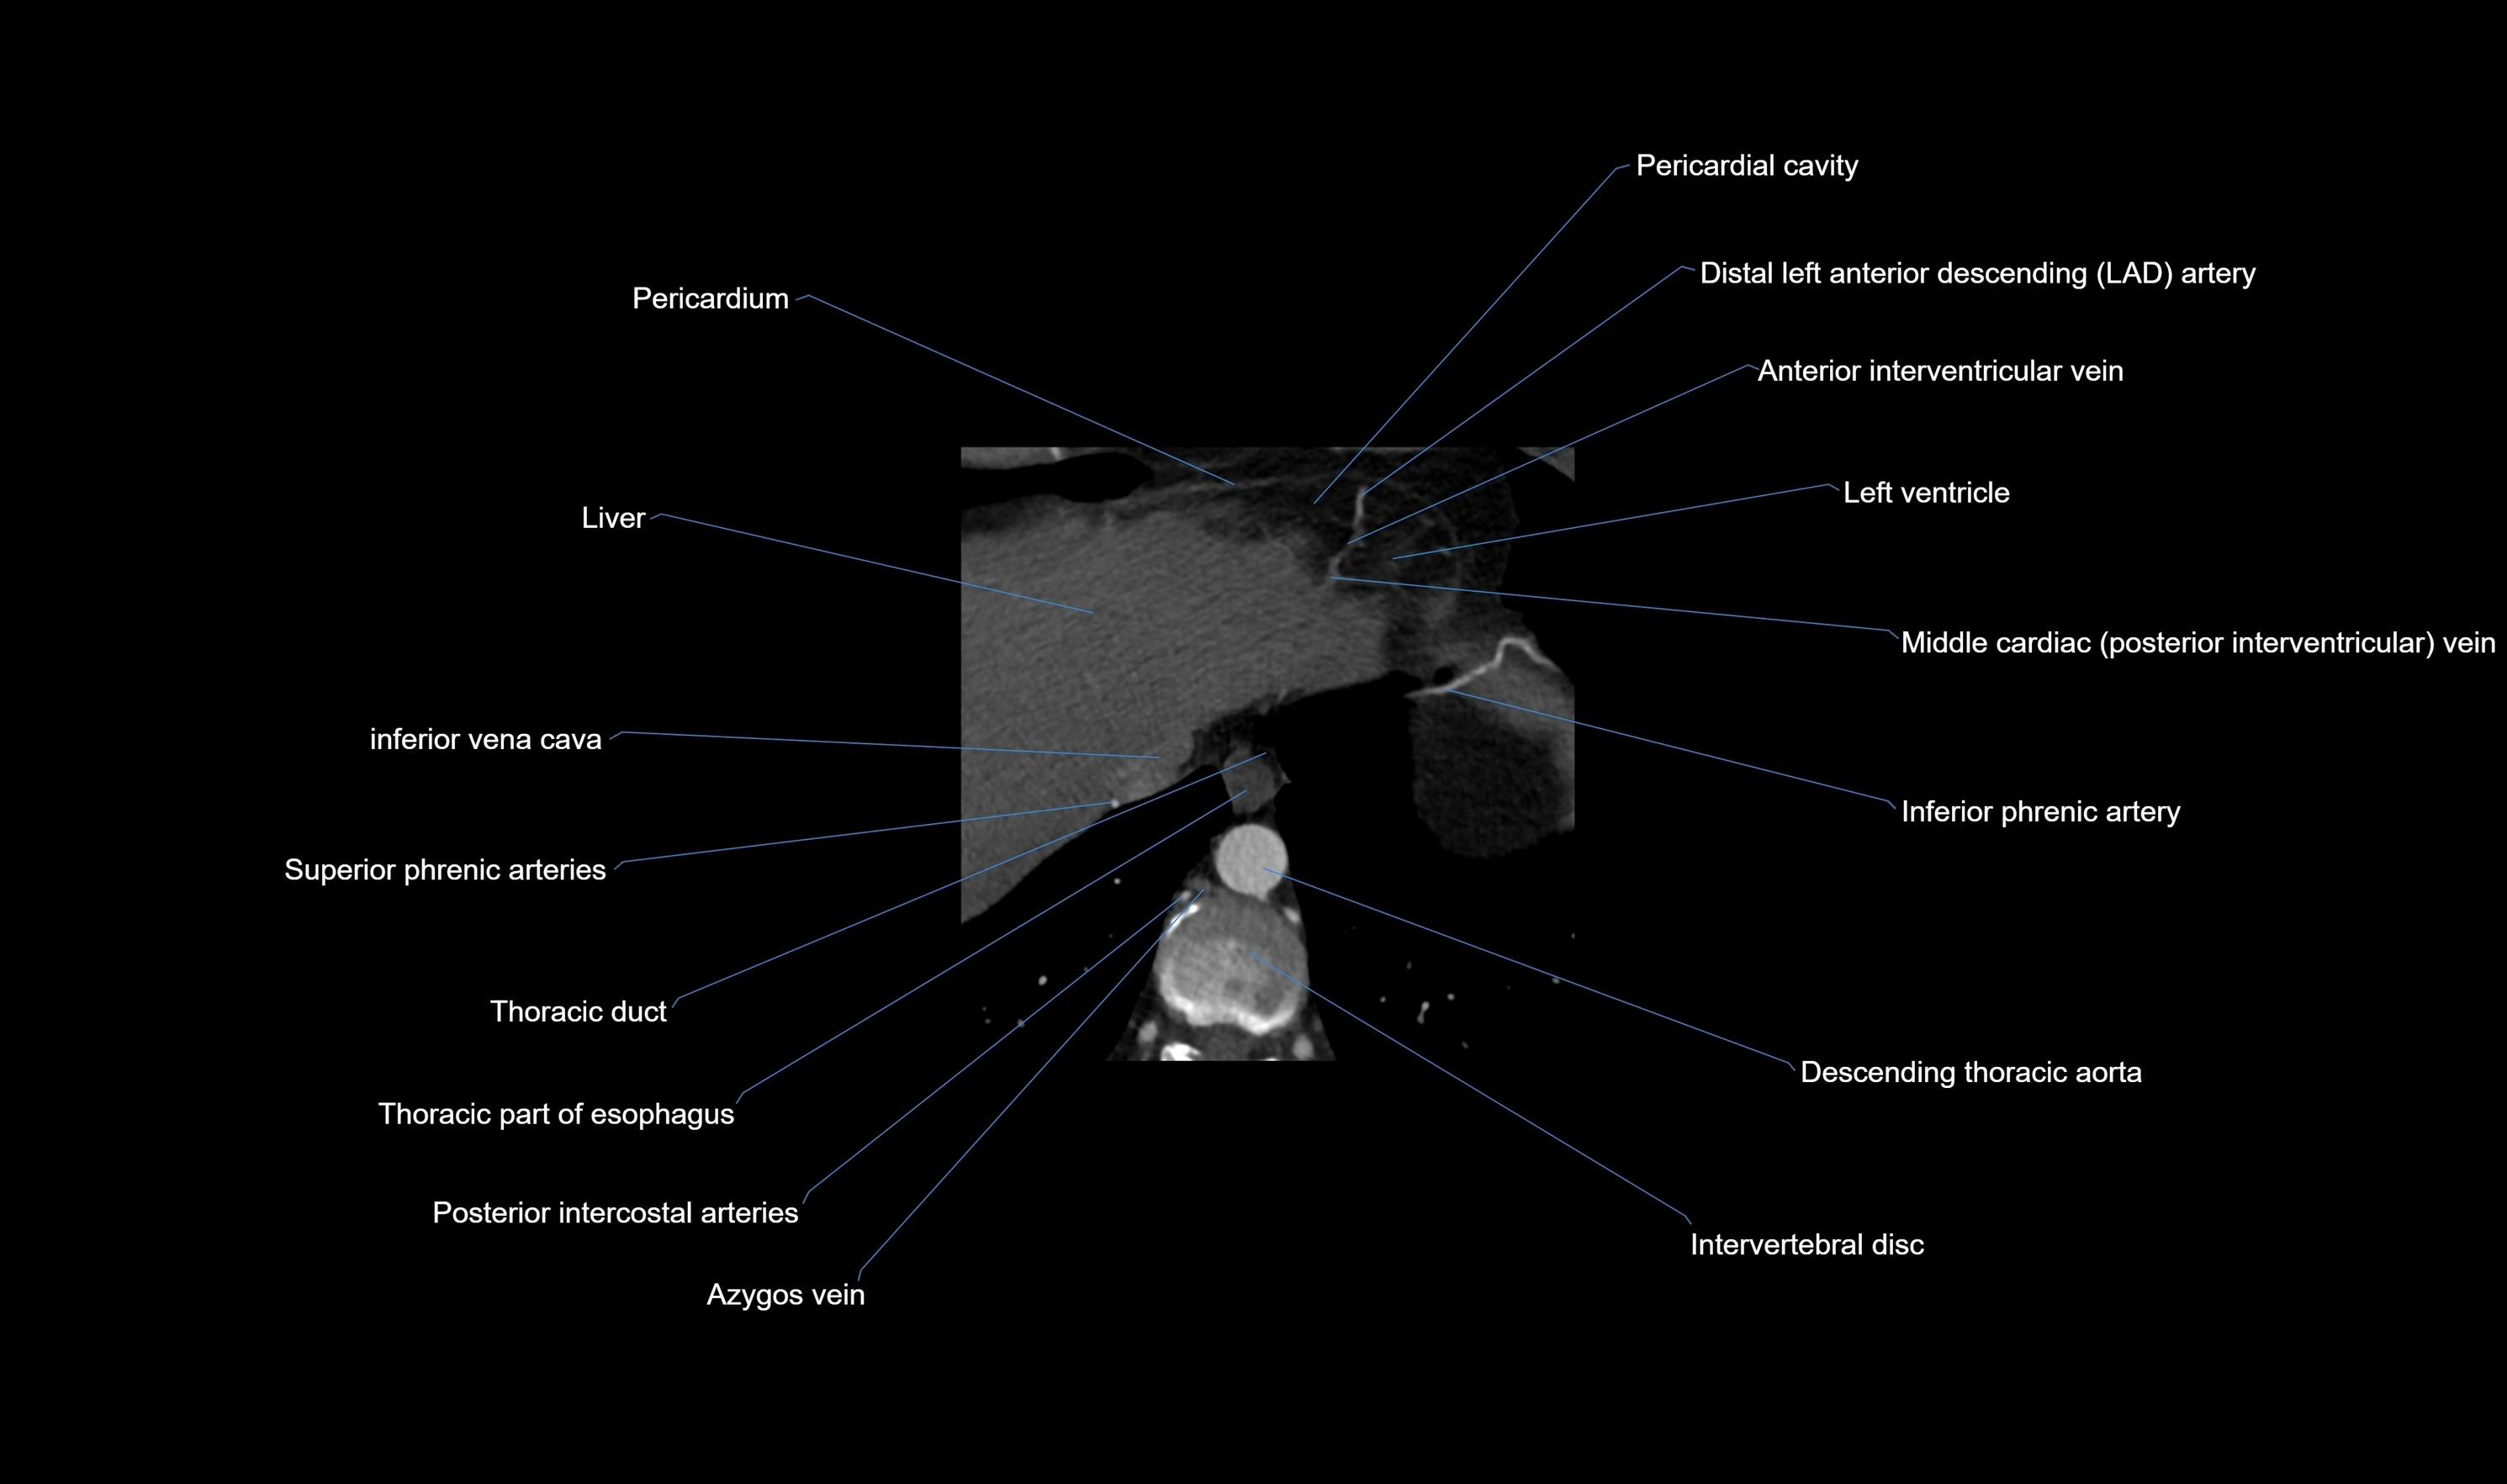

CT images